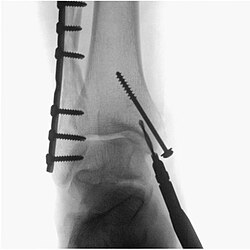

Primjena rendgenskog zračenja većinom se zasniva na prodiranju zračenja kroz kemijsku tvar. Što su atomi neke tvari veće mase, to jače upijaju (apsorbiraju) rendgensko zračenje: olovo jače nego aluminij, kalcij u kostima jače nego ugljik, kisik i vodik u mišićima. To se svojstvo primjenjuje kako bi se učinila vidljivom unutrašnjost tijela. [1]

Pri apsorpciji se kvant rendgenskog zračenja dijelom troši na udaljavanje elektrona iz njegove ljuske. Na taj se način rendgensko zračenje pretvara u druge oblike energije, kao što su svjetlosna ili toplinska energija. Koeficijent apsorpcije proporcionalan je gustoći tvari kroz koju zračenje prolazi, atomskom broju elementa i valnoj duljini. Prema tome, rendgenskog zračenja kraćih valnih duljina ili tvrdo rendgensko zračenje, bit će manje apsorbirano, dakle je prodornije od onoga duljih valnih duljina. Prolaskom kroz nehomogeno tijelo rendgensko zračenje se više apsorbira na mjestima veće gustoće i na mjestima koja su od elemenata većeg atomskog broja. Upravo ta pojava primjenjuje se u medicinskoj dijagnostičkoj radiografiji, kod snimanja kostiju.

Medicinska radiologija i radiografija

Projekcijska radiografija i dijaskopija prikazuju snimani dio tijela kao sumaciju sjena nastalu projekcijom iz jedne točke, žarišta rendgenske cijevi. Nejednakim slabljenjem rendgenskog snopa u različitim organima i tkivima nastaje virtualna slika snimanog dijela tijela koju receptor slike pretvara u vidljivi radiogram. Receptor slike može biti analogni, primjerice film-folijski sustav, odnosno luminiscentno pojačalo na dijaskopskim uređajima ili digitalni.

U radiološkoj dijagnostici zrače uređaji za rendgensko snimanje (primjerice, za snimanje kostiju ili pluća), uređaji za dijaskopiju (primjerice za pregled želuca, irigografija) i uređaji za računalna tomografiju (CT). Magnetska rezonancija i ultrazvuk ne koriste štetno ionizirajuće zračenje za oslikavanje ljudskoga tijela. Ipak, magnetska rezonancija može biti opasna kod metalnih stranih tijela ili ugrađenog pace-makera. Nažalost, niti jedna od metoda ne pokriva sve dijagnostičke potrebe. Odabir dijagnostičke pretrage treba prepustiti liječniku koji će odrediti najkraći put do točne dijagnoze, uz najmanju štetu za zdravlje bolesnika.